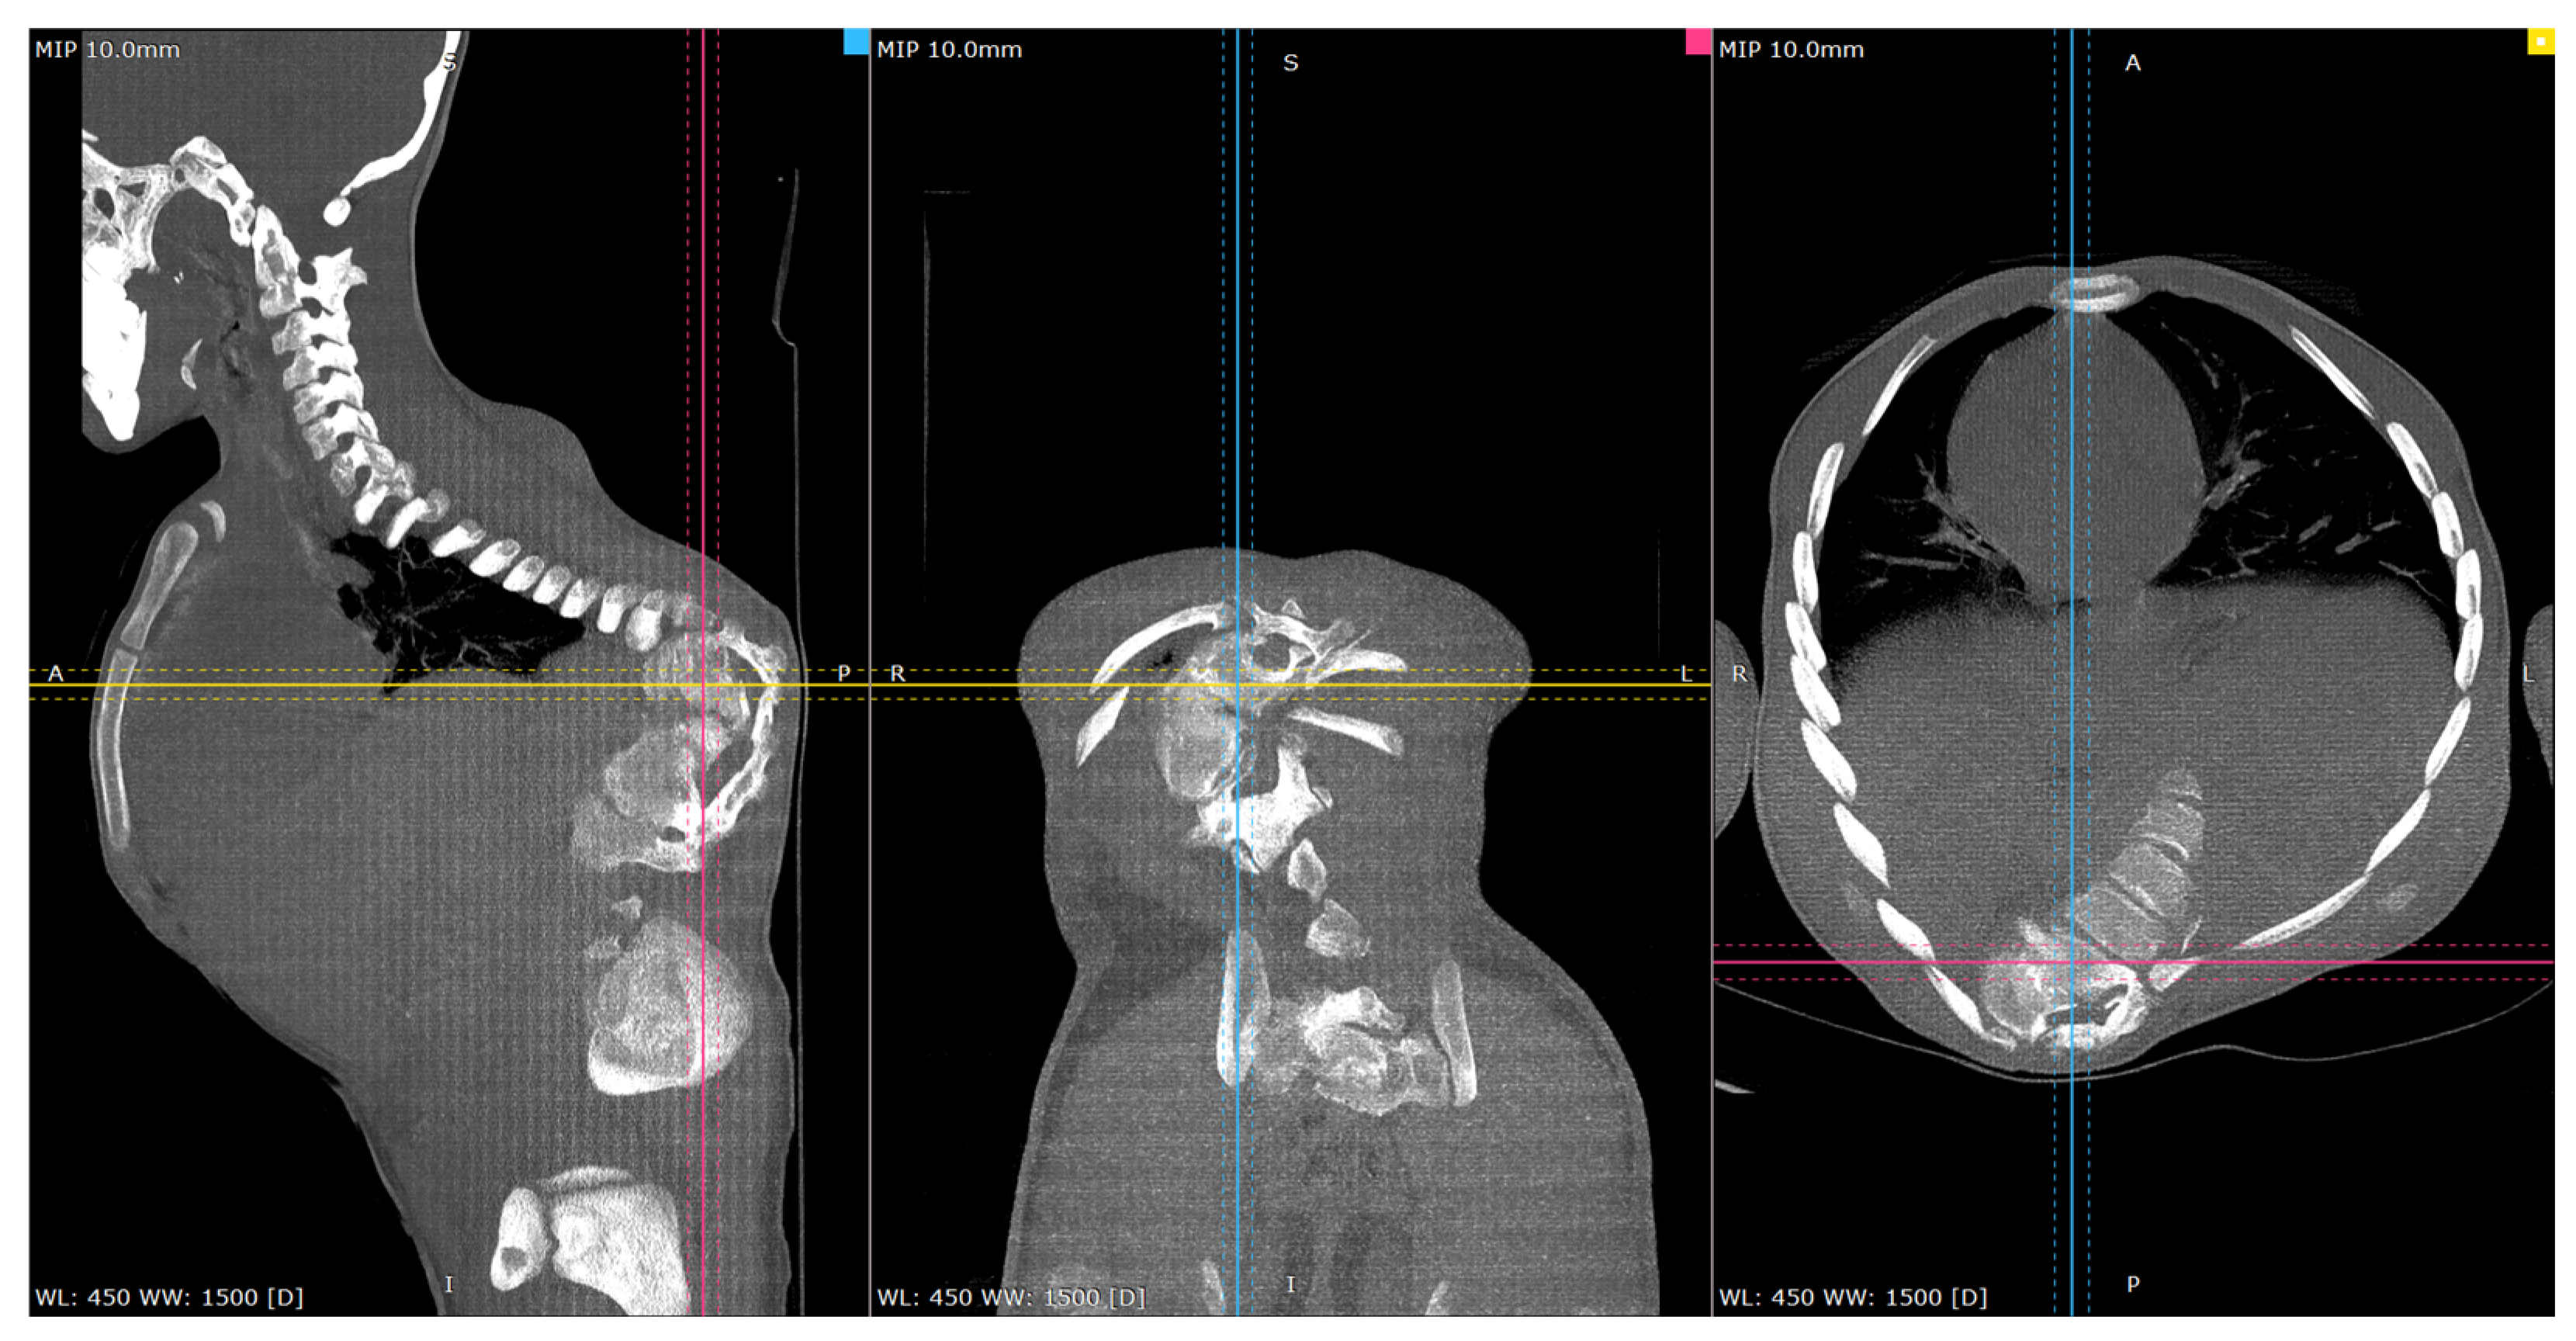

Figure 4.

Representative pre-op CT scan views of the congenital deformity. Cross-reference grid lines mark the intersection of the corresponding image planes: Blue—sagittal; Pink—Coronal; Yellow—Axial views.